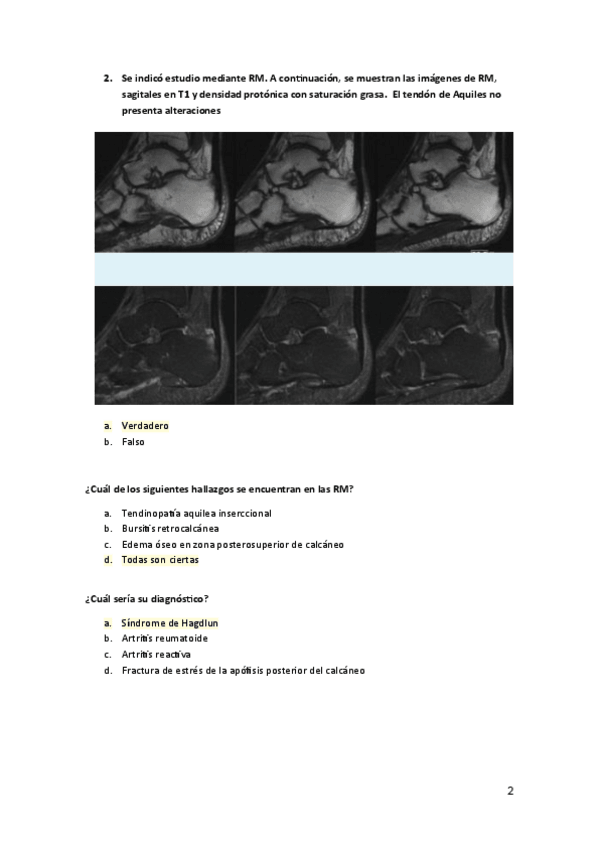

He publicado nuevos examenes de 3º Radiodiagnóstico y radioprotección: AUTOEVALUACION-RADIODIAGNOSTICO-CASOS-CLINICOS.pdf

28 páginas